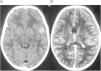

Niño de 7 años sin antecedentes personales de interés que consulta por cefalea holocraneal de un mes de evolución, con vómitos matutinos. No refieren ningún traumatismo craneal reciente. Se realiza fondo de ojo en el que se aprecia edema de papila bilateral. En la tomografía computerizada (TC) craneal realizada a continuación se observa una lesión hiperdensa en cisura de Silvio (fig. 1-A). En la TC con contraste, se aprecia un hematoma subdural subagudo-crónico hemisférico izquierdo, con moderado efecto masa que desplaza línea media (fig. 1-B). En la RM craneal se aprecia una colección extra-axial en lóbulo temporal izquierdo y cisura de Silvio con contenido hemático comunicado con el hematoma subdural (figs. 2 y 3), compatible con quiste aracnoideo complicado. Se realiza craneotomía izquierda urgente con evacuación completa del hematoma subdural, siendo alta a los cinco días sin secuelas neurológicas. La angio-TC realizada 15 días más tarde descarta aneurismas cerebrales u otras causas de sangrado, persistiendo una imagen compatible con quiste aracnoideo silviano izquierdo. Actualmente el niño está asintomático, con seguimiento ambulatorio.